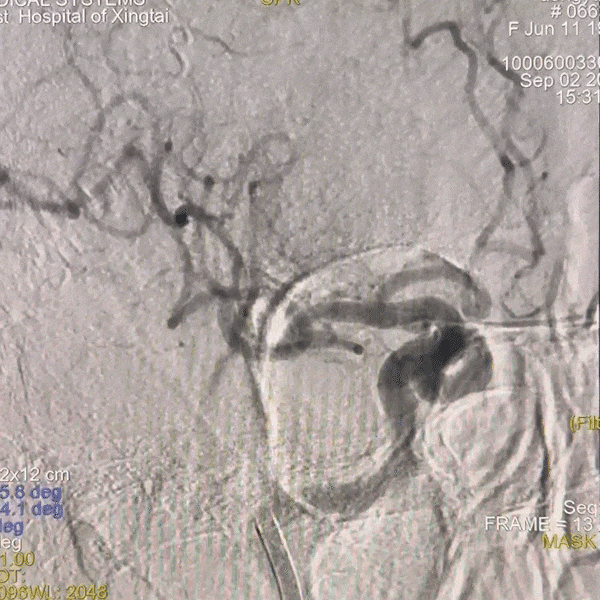

手术过程

通路建立:经桡造影显示Ⅲ型弓,病变为右侧颈内动脉C4段动脉瘤,患者桡动脉纤细不适合经桡治疗,故选择经股动脉应用赛诺神畅APEX TRA GC™5F-130 SIM2导引导管超选右颈,同轴长鞘建立通路。

跟进长鞘至右侧颈内动脉。

动脉长鞘怎么置入一技之“长”丨经桡及经股困难入路应用赛诺神畅APEX TRA GC™导引导管建立通路病例合集_https://www.jmylbn.com_新闻资讯_第23张

栓塞动脉瘤;致密栓塞AN后复查造影。

动脉长鞘怎么置入一技之“长”丨经桡及经股困难入路应用赛诺神畅APEX TRA GC™导引导管建立通路病例合集_https://www.jmylbn.com_新闻资讯_第24张

动脉长鞘怎么置入一技之“长”丨经桡及经股困难入路应用赛诺神畅APEX TRA GC™导引导管建立通路病例合集_https://www.jmylbn.com_新闻资讯_第25张